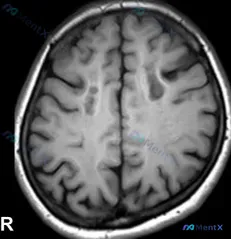

- 灰白质对比尚可,脑中线居中,无明显占位效应。

- 重点:双侧额顶叶皮层下及深部白质(半卵圆中心层面)可见多发散在斑点状、小类圆形低信号灶,信号略低于周围正常白质,边缘清晰,无周围水肿。

- 未见明显急性出血或大血管异常。